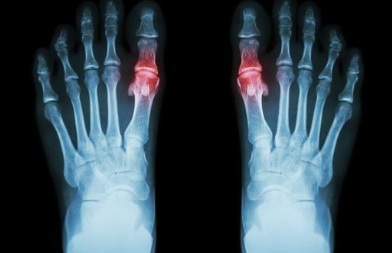

河南痛风关节炎专科医院:痛风一般发生在什么部位?

河南痛风关节炎专科医院介绍到痛风最常发生在第一跖趾关节,左右可以交替出现。最刚开始发…[详情]